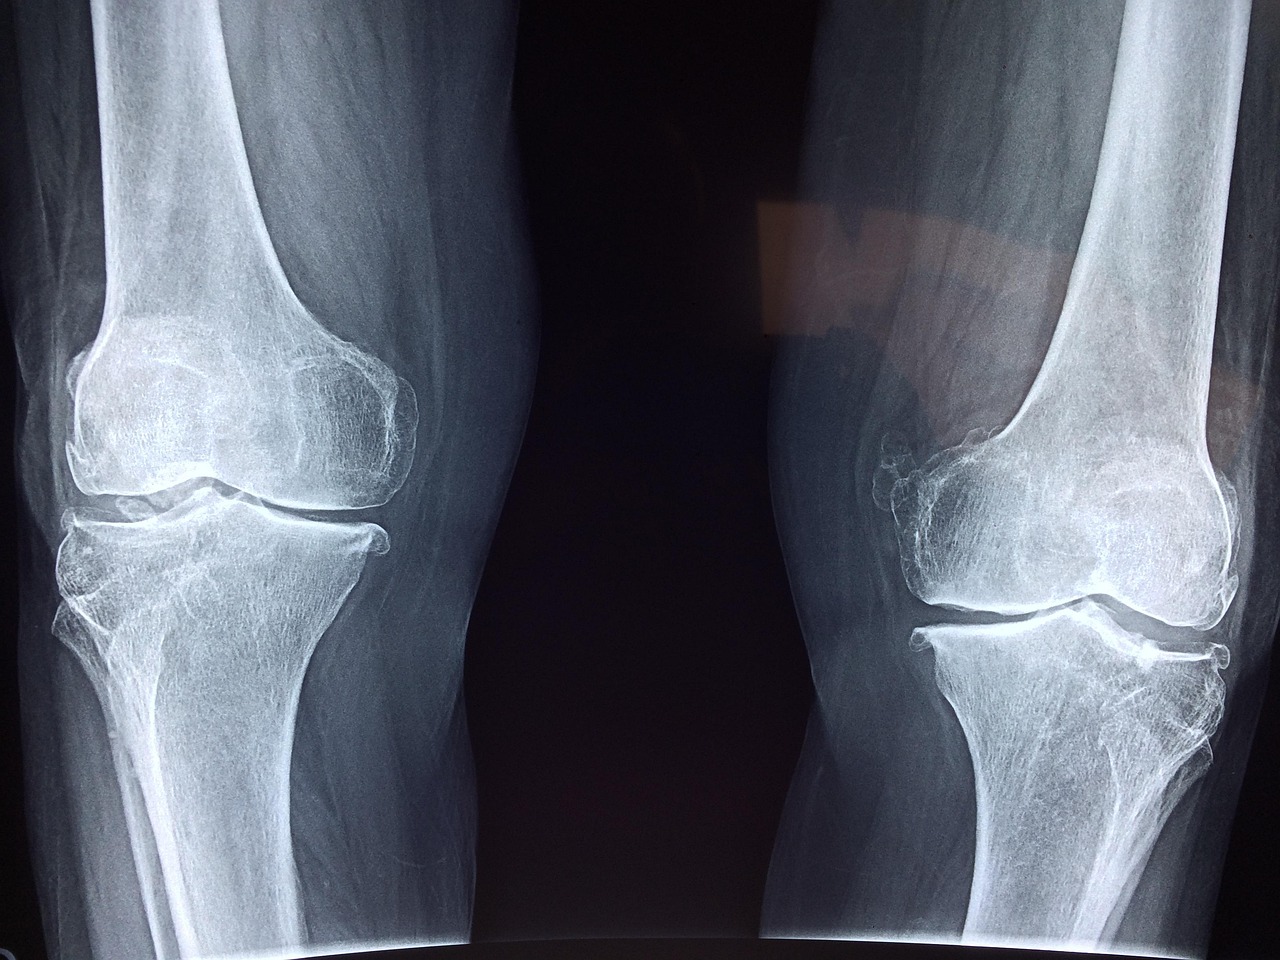

Obrazowanie rentgenowskie stawu kolanowego umożliwia wykrycie szerokiego spektrum schorzeń oraz urazów, które mogą być przyczyną dolegliwości bólowych lub ograniczenia ruchomości. Najczęściej diagnozowane patologie to zmiany zwyrodnieniowe, prowadzące do uszkodzenia chrząstki stawowej i deformacji powierzchni kości. RTG pozwala również na precyzyjne rozpoznanie złamań kości, zarówno świeżych, jak i tych w fazie zrostu, co jest szczególnie istotne po przebytych urazach lub zabiegach ortopedycznych.

Za pomocą zdjęcia rentgenowskiego możliwa jest także ocena obecności reumatoidalnego zapalenia stawów, dny moczanowej czy przewlekłej niestabilności kolana. Charakterystyczne zmiany radiologiczne, takie jak zwężenie szpary stawowej, nadżerki kostne czy obecność złogów kryształów kwasu moczowego, stanowią cenne wskazówki diagnostyczne dla lekarza. RTG znajduje zastosowanie nie tylko w rozpoznaniu pierwotnym, ale również podczas monitorowania postępów leczenia – kontrolne zdjęcia pozwalają ocenić efekty terapii i ewentualną progresję choroby. W przypadku podejrzenia innych patologii, takich jak guzy kostne czy infekcje stawu, prześwietlenie stanowi pierwszy etap diagnostyki przed skierowaniem na bardziej zaawansowane badania obrazowe.